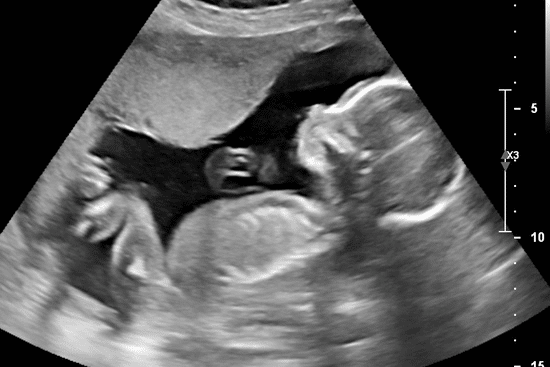

Als we thuiskomen besluit ik in bad te gaan. Dat kan helpen om beweging te voelen. Ik ben 28 weken zwanger vandaag, ik zou hem nu toch echt elke dag moeten voelen. Het is mijn eerste zwangerschap, alles is nieuw voor me. Maar de gehele zwangerschap was nog niet onbevangen voor mij. Hoe komt dat toch. Bij de eerste echo was ik bang dat ik een niet kloppend hartje zou zien. Toen ik 20 weken was begon ik af en toe oud bloed te verliezen, maar ook daar was niets aan de hand. Ik ben al een keer op een extra controle geweest op zondag, omdat hij toen ook rustig was en ik geen beweging voelde. Ze zullen me inmiddels vast een overbezorgde mama-to-be vinden daar bij de verloskundigenpraktijk…

De volgende morgen voel ik nog steeds geen leven. Ik heb zelf een doppler besteld gisteren online, die komt vandaag binnen. Ik moet gewoon weten of het hartje nog klopt. Ik besluit mijn zus te bellen voor advies. Ze is kraamverzorgster, ze kan me vast gerust stellen. Maar helaas, ze zegt dat ik echt naar de verloskundigenpraktijk moet bellen. Ik vertel haar nog dat ik een doppler heb besteld, maar zij adviseert me deze niet te gebruiken en echt naar de verloskundige te bellen. Dus ik bel. Ik vertel de telefoniste dat ik al ruim een dag geen leven meer heb gevoeld en dat ik 28 weken zwanger ben. Ze gaat overleggen. Ik kijk op mijn horloge… het is 9.15 uur. Ik hoop dat ik snel terecht kan. De telefoniste komt weer terug aan de telefoon. Ze zegt dat ik ’s middags om 14.45 uur mag komen. Wat moet ik lang wachten denk ik, maar goed, blijkbaar maak ik me dan toch zorgen om niets, anders zouden ze mij toch wel meteen laten komen? En hoe kom ik de komende uren door?